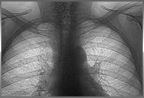

Медики призывают торговцев пройти флюорографию прямо на рабочем месте. 14 и 15 августа противотуберкулезный диспансер устанавливает передвижной флюорограф на рынках Шыгыс и Алтын Арба. Завтра в среду обследоваться смогут работники рынка Шыгыс. 15-го августа в четверг флюорографию прямо на рабочем месте могут пройти продавцы Алтын Арбы. Медики готовы поставить печать в санитарную книжку и отдать снимок. Обследование будет проходить с 10 до 16 часов. Все это делается в целях профилактики туберкулеза. |